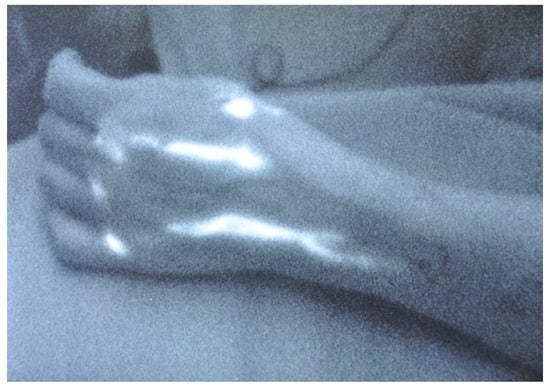

Figure 4.

LVA was performed successfully in an end-to-end fashion. The patent blue on the subdermal venule shows the patency of LVA.

Figure 5.

(a) Patient with right upper extremity lymphedema stage 1; (b) patient treated with 3 LVA. A reduction in the interlimb volume from 34% to 12% was achieved.

The goal of lymphaticovenular anastomosis (LVA) is to restore lymphatic circulation by connecting functional lymphatic channels to subdermal venules of similar size, creating peripheral shunts within the lymphedematous limb. This allows for unidirectional flow from the congested high-pressure lymphatic system to the lower-pressure venous system [30]. To achieve successful long-term LVA, certain principles must be followed. Candidates for LVA must have functional or at least draining lymphatic vessels and a venule in proximity without reflux. As described before, there are many imaging modalities available to evaluate the functional status of lymphatics and, consequently, to predict the outcome of LVA. The most used modality is ICG-L. Since all of the lymphatic pathways do not deteriorate concurrently or to the same extent, early-stage patients are more likely to have functional lymphatics in superficial distribution that are easily visualized via ICG-L. On the other hand, patients in advanced stages may benefit from methods such as MRL or SPECT/CT to reveal deeper functional lymphatics. Therefore, the integration of different imaging modalities (ex., ICG-L and MRL) increases the reliability of the preoperative localization of functional lymphatics and may predict the outcome of LVA. Regarding the existence of a venule in proximity without reflux, as dynamic venous stenosis may contribute to lymphedema, some authors recommend screening for venous compression or reflux as part of the perioperative evaluation. This allows for the evaluation of the utility of scar fibrosis release, angioplasty, or venous stenting in the treatment of venous insufficiency [31,32]. A meticulous surgical technique is critical for a successful long-term LVA [26]. At selected cutaneous sites, two-centimeter skin incisions are made, and lymphatic channels and venules are carefully dissected under a microscope using super-microsurgery instruments. Nylon sutures of 11–0 or 12–0 are used for the anastomosis, and the anastomotic technique is selected depending on the relative calibers of the vessels found. Veins and lymphatics can mainly be anastomosed in the end-to-side, end-to-end, side-to-side, and side-to-end arrangements. The most efficient bypass is considered by some authors to be the side-to-end arrangement, as it allows for bidirectional lymph flow into a recipient vein while preserving the native lymph flow of the vessels and preventing damage to existing vessels [6]. However, there is no established consensus regarding the best technique to use or the number of anastomoses to perform [33,34]. After performing the anastomosis, its patency can be tested with ICG-L or patent blue dye (Figure 4). LVA is more effective in patients with early stages of lymphedema, although there can be a synergistic benefit when performed synchronously with vascularized lymph node transplantation in advanced-stage lymphedema. In fact, lymphedema treatment is a highly individualized process, and its effectiveness is consistently enhanced in combined approaches [30]. The eligibility of the LVA procedure is mainly determined by the presence of healthy, functional lymphatic vessels rather than the stage of lymphedema [32,35]. LVA can also be helpful in the treatment of lymphorrhea, as demonstrated by some studies [36,37]. The complications of LVA are minimal, with rates reported at 5.9% [30]. LVA offers significant advantages for the patient, being a minimally invasive procedure that can be performed as an outpatient procedure under local or general anesthesia, with a short recovery time and minimal postoperative restrictions [32] (Figure 5).